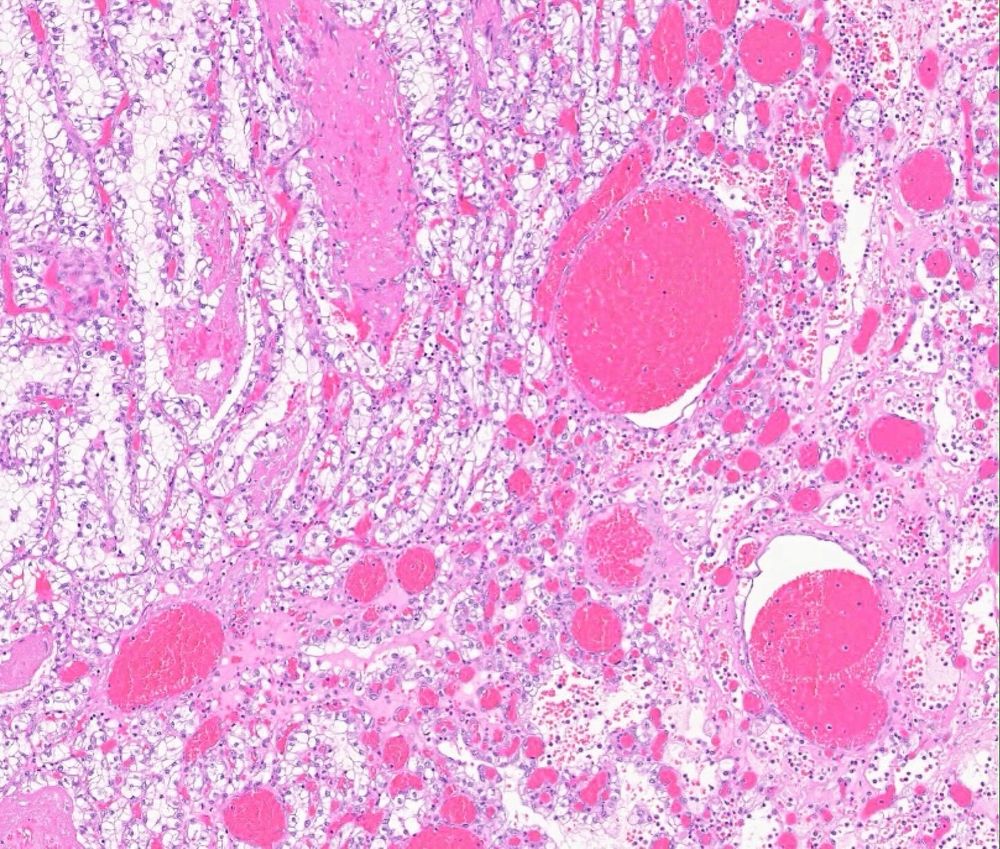

#slidearchiveseries urothelial carcinoma in situ colonizing prostatic urethra #gupath